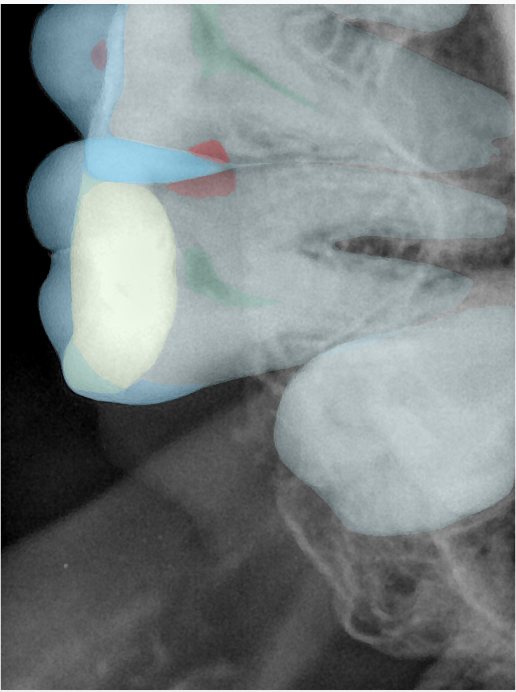

CR/DR 牙齿分割阶段记录

当前进展

- 完成了 CR/DR 牙齿相关分割训练

- 当前结果已经达到阶段预期,但仍有细节问题需要继续处理

相关测试

遇到的问题

- 训练过程中出现过 mask 下移问题

- 部分结果会出现 box 填充异常

- mask 边缘仍然有比较明显的锯齿感

参考

第二版算法问题测试

| 第一版 | 第二版 | 是否解决 | |

|---|---|---|---|

![]() | ![]() ![]() 边角识别有问题 龋齿识别不全 牙髓识别不全 | ![]() | 解决 |

![]() | ![]() 边角识别有问题 识别信息有误 自查(牙冠识别不全) | ![]() | 解决 |

![]() | ![]() ![]() 边角识别有误 大范围填充识别遗漏 | ![]() | 解决 |

![]() | ![]() 识别信息不全 | ![]() | 解决 |

![]() | ![]() ![]() 边角问题 牙胶识别不全 牙冠识别不全 | ![]() | 解决 |

![]() 换图片 | ![]() | ![]() 牙冠部分稍微白了一些就识别成小范围修补,部分判断异常 | 部分解决,修复类略敏感,牙冠部分稍微白了一些就识别成小范围修补,部分判断异常。 |

![]() | ![]() ![]() 牙冠识别不全 牙髓不全 根尖炎龋齿识别有误 | ![]() | 解决 |

![]() | ![]() | ![]() | 解决 |

![]() 换图片 | ![]() | ![]() | 解决 |

![]() | ![]() 牙冠识别有误 | ![]() | 解决 |

![]() 换图片 | ![]() ![]() 边角识别有误 | ![]() 修复类敏感 | 部分解决,图像过白,导致修复类判断异常。 |

![]() 换图片 | ![]() 牙冠识别不全 | ![]() 修复类敏感 | 部分解决,图像过白,导致修复类判断异常 |

结论:修复类出现了不鲁棒的情况,后续需要加入轮廓的扩充数据进行增强。